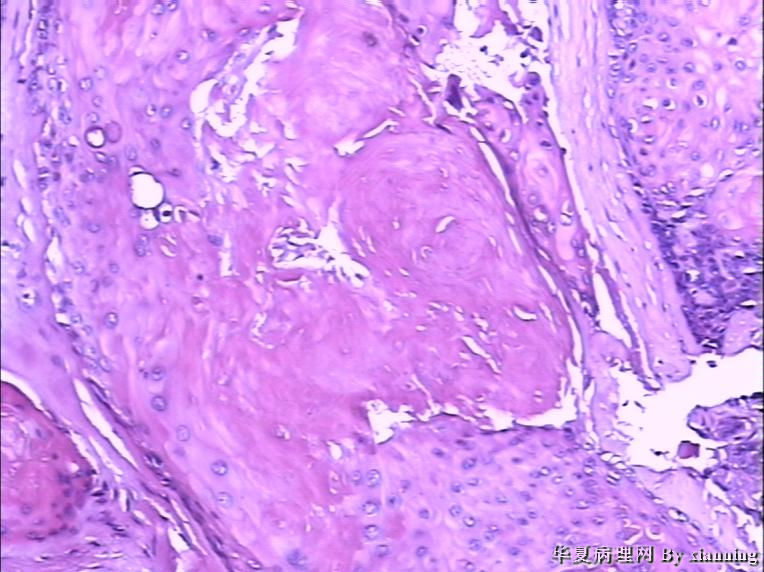

女 50岁 头皮下肿块

巨检:灰白色不规则结节0.9*0.7*0.4cm3,切面灰白色实性质地中等

名称:图2

描述:36580004